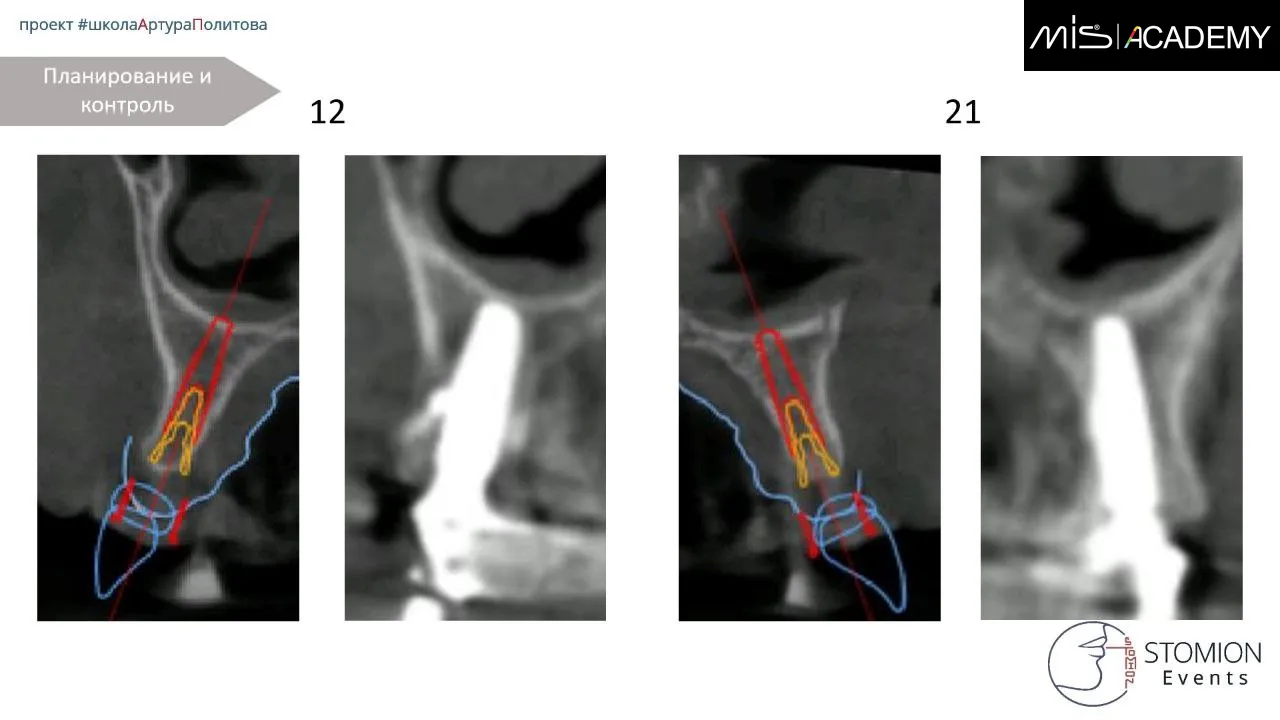

— Установка имплантатов MiS C1 в позициях 6-4-2-1-4-6.

— 1.6, 1.4, 2.4 — угловые МЮ,

— 1.2, 2.1 — коннекты,

— 2.6 — прямой МЮ.

— Колено угловых МЮ ориентированы либо строго по дуге, либо нёбно.

При установке получилась вестибулопозиция имплантата 1.2, уже не помню причину, думаю смещение за счёт нёбной стенки, помню, что принято решение не менять позицию, конструкция будет под винт изибэйс для винтовой фиксации.